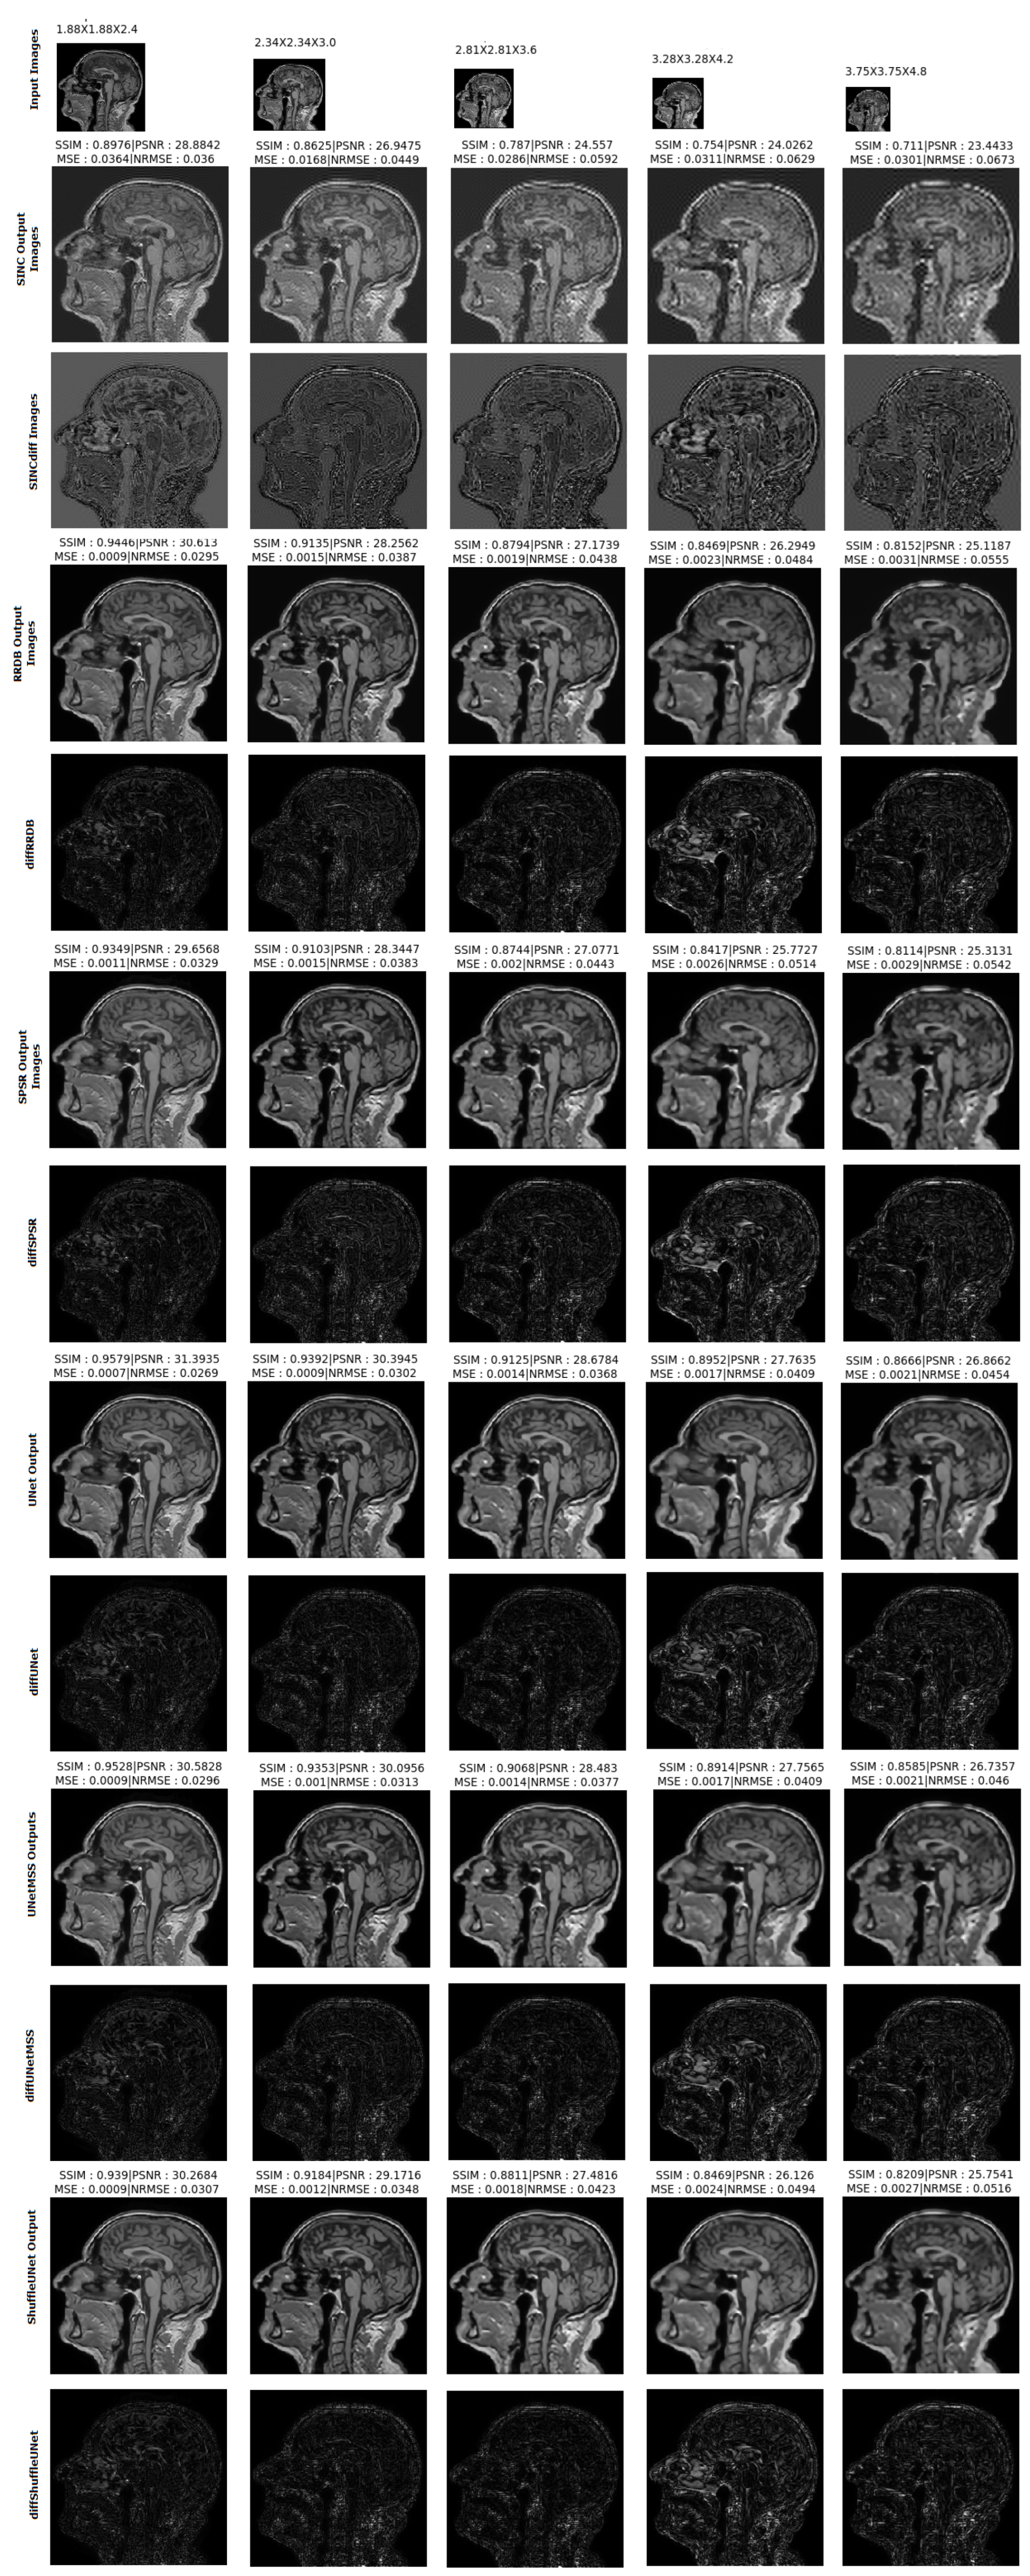

- Visualising individual model results for all the acceleration factors.

Different 3D CNN Models Results Comparison for Cross Acceleration Factor of IXI-T1 Dataset